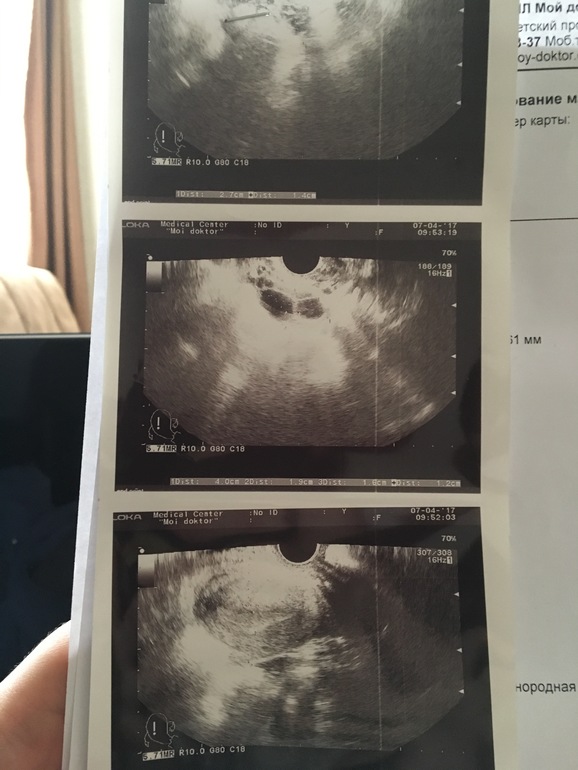

Девочки посмотрите узи понимающие

Овуляция( тесты на овуляцию)Это разве не Жт? как тогда 4 апреля мне врач на узи жт увидел и я его видела своими глазами, а вчера врач другой написала в заключении что это фолликулы?

это узи за вчера

это за 4 апреля

вот я сама в шоке а вы по фото не видите ? есть жт? я вся извелась задержка 6 дней ов поздняя, и мучают эти узисты ужасно,